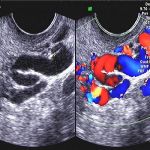

这种疼痛有别于其他性质的腹痛,它是与月经相关的疼痛,表现为经期腹痛或者是来月经前、后痛,特点是继发性痛经,即原来不疼后来突然疼痛,大部分是子宫内膜异位症和子宫腺肌症导致的。就是类似于子宫内膜的细胞出现在了盆腔、子宫肌壁间、卵巢甚至人体的某些管道和腔道里头,它们随着体内激素水平变化的时候也发生于类似子宫内的变化,如脱落、坏死、出血会引起局部刺激而导致疼痛,甚至有性交痛。